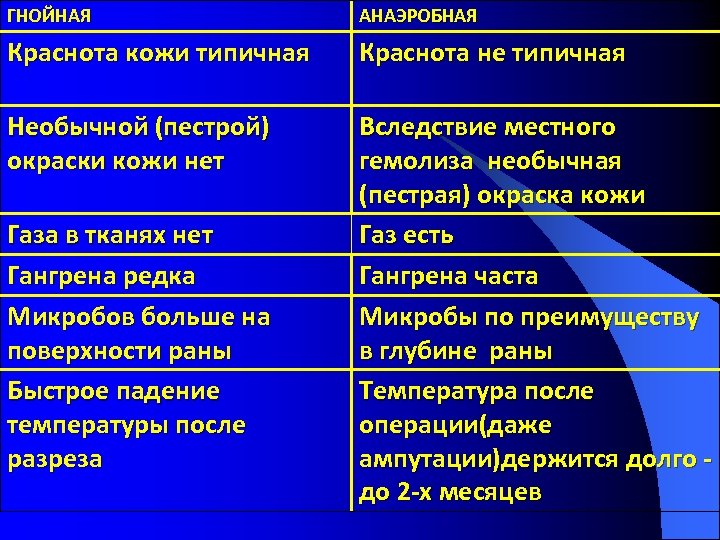

ГНОЙНАЯ АНАЭРОБНАЯ Краснота кожи типичная Краснота не типичная Необычной (пестрой) окраски кожи нет Вследствие местного гемолиза необычная (пестрая) окраска кожи Газ есть Гангрена часта Микробы по преимуществу в глубине раны Температура после операции(даже ампутации)держится долго до 2 -х месяцев Газа в тканях нет Гангрена редка Микробов больше на поверхности раны Быстрое падение температуры после разреза

ГНОЙНАЯ АНАЭРОБНАЯ Краснота кожи типичная Краснота не типичная Необычной (пестрой) окраски кожи нет Вследствие местного гемолиза необычная (пестрая) окраска кожи Газ есть Гангрена часта Микробы по преимуществу в глубине раны Температура после операции(даже ампутации)держится долго до 2 -х месяцев Газа в тканях нет Гангрена редка Микробов больше на поверхности раны Быстрое падение температуры после разреза